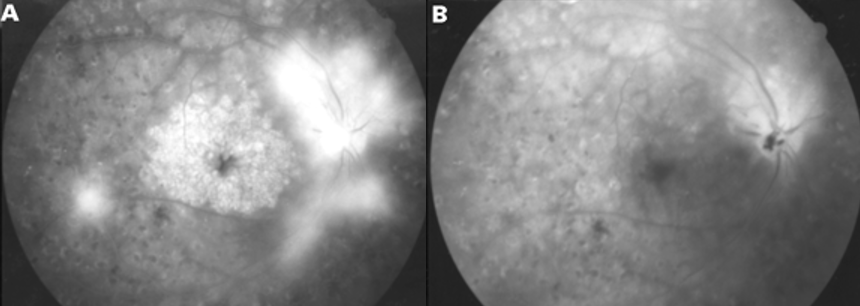

그림6.(A) 수술 전 전형적인 CME의 FAG 누출을 확인할 수 있으며, (B)유리체절제술 1개월 후 실시한 FAG에서 꽃 모양누출과 시신경 부위의 누설이 확실히 줄어든 것을 알 수 있습니다.3) CME를 일으키는 인공수정체를 제거하고 다른 것으로 대체하는 방법도 있습니다.남들이 하는 백내장 수술, 하면 다들 세상이 밝아진다고 들었는데 왜 나는 잘 보이지 않을까.어떤 수술이든 부작용과 합병증은 있어요. 100% 안전한 수술이 있다면 그 질환은 수술로 해결할 수 있기 때문에 더 이상의 연구도 필요 없을 것입니다.보다 안전한 수술, 수술을 받는 사람과 하는 사람 모두에게 부담을 덜 수 있는 방향을 찾기 위해 사람들은 계속 연구하고 발전해 나갈 것입니다.그러기 위해서는 지금의 문제, 현황을 잘 알고 있는 것이 중요하다고 생각합니다. 그래서 오늘도 어려운 눈이야기를 함께 공부해 보았습니다.수고하셨습니다!